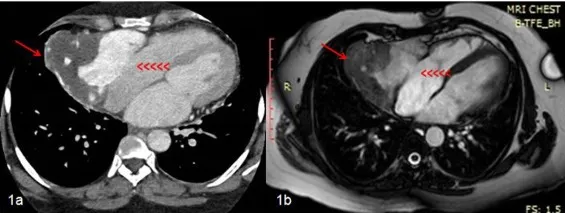

Beyond coronary imaging, cardiac CT excels at evaluating cardiac masses, pericardial disease, and congenital anomalies with spatial resolution surpassing echocardiography and MRI for specific applications.

These CT anatomical insights complement tissue characterization capabilities through cardiac MRI to provide comprehensive structural and functional assessment.

Cardiac magnetic resonance imaging (CMR) delivers unparalleled soft tissue contrast and functional assessment without ionizing radiation, achieving gold-standard accuracy for ventricular volumes (±5 mL), ejection fraction (±3%), and mass quantification (±10 g). Late gadolinium enhancement (LGE) detects myocardial scar with 95% sensitivity, distinguishing ischemic from non-ischemic cardiomyopathy patterns and guiding implantable cardioverter-defibrillator (ICD) placement when scar burden predicts arrhythmic risk.